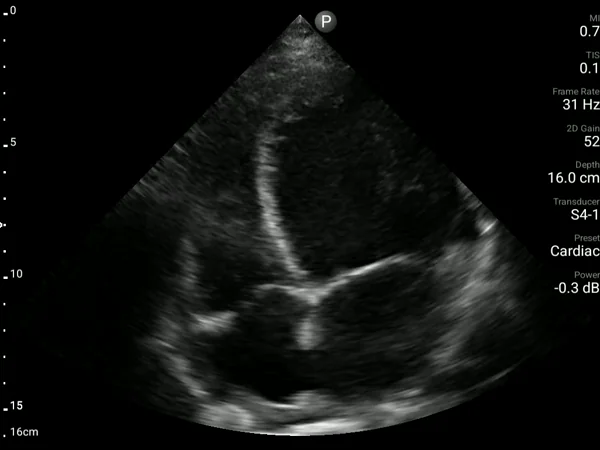

A 39-year-old woman with APLA syndrome returned to the ED three weeks after an emergency C-section with recurrent chest pain. Pulmonary embolism had been ruled out during a visit two days earlier, and an echocardiogram performed two months prior was normal (EF 60%).

A bedside AISAP exam revealed severe LV dysfunction, moderate RV dysfunction, severe MR, and mild pericardial effusion. These findings led to an urgent formal echocardiography and cardiology review, which established the diagnosis of postpartum cardiomyopathy.